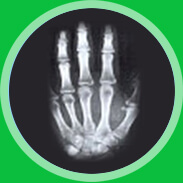

天使特色骨龄读判技术—准确测试骨龄 了解身高发育状况

骨龄是判断孩子生长潜力的标准骨龄测定能够判断骨龄成熟的程度及预防孩子将来的身高。

仪器扫描左手x线片。

拥有30余年临床经验的矮小症医生进行x线片的解读,确保检测结果的准确性。

在关节和关节之间可清晰的看到软骨层及缝隙,手掌下段小骨头之间的缝隙并没有完全融合,这说明骨骺还没完全融合,还具有生长潜力。

关节和关节之间的软骨层没有了,缝隙变得很紧密,手掌下方小骨头间的缝隙完全融合,这说明骨骺已完全融合,已没有任何生长潜力。